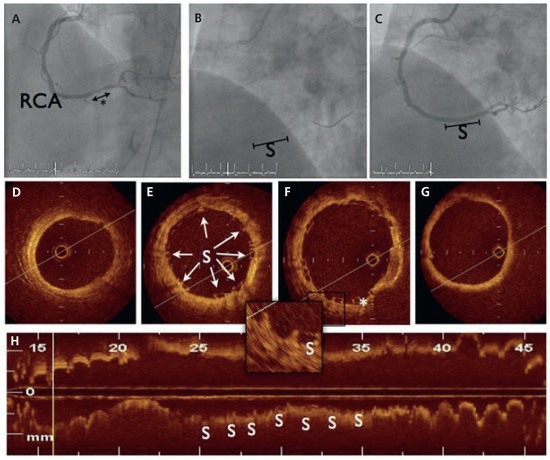

Figure 1.

Angiographic and optical coherence tomography (OCT) findings during index procedure. (A) Dye injection in the right coronary artery (RCA) demonstrated one 10 mm-stenosis of the distal part (*). (B) BVS scaffold platform is radiolucent but two small platinum markers allow accurate placement of the device. (C) Final angiogram after scaffold implantation. (D–G). Cross-sectional OCT imaging from distal to proximal: the BVS struts (S) are discernible with sites showing sharply defined, bright reflection borders, usually described as having a “box-shaped” appearance (arrows). One strut was not apposed to the vessel wall (*). (H) Longitudinal reconstruction.